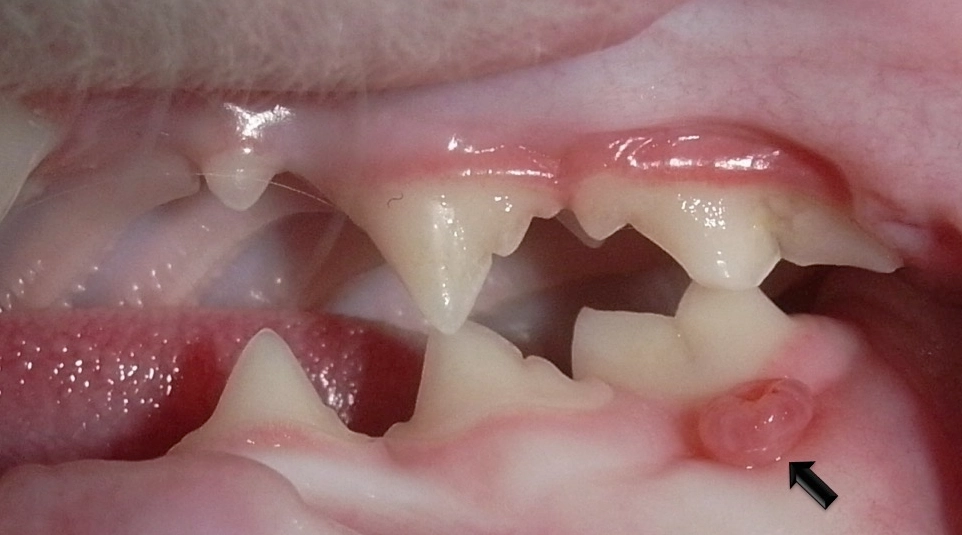

親身觀察:阿肥的牙結石是黃褐色的,主要堆積在後臼齒的外側。獸醫用探針輕碰牠紅腫的牙齦,阿肥立刻有閃躲反應,這表示已經有疼痛感了,但牠平時忍著沒表現出來。

這是一種讓貓非常痛苦、也讓飼主和獸醫頭痛的嚴重免疫性疾病。貓咪的口腔黏膜(包括牙齦、舌側、喉嚨後方)會出現嚴重的、瀰漫性的發炎、紅腫、潰瘍。它的紅腫範圍更廣,程度更劇烈,常常連喉嚨都腫起來,導致貓咪無法進食。病因複雜,可能與貓卡里西病毒、貓免疫缺陷病毒等有關,但普遍認為是貓咪自身的免疫系統對牙菌斑中的細菌產生過度激烈的反應所導致。